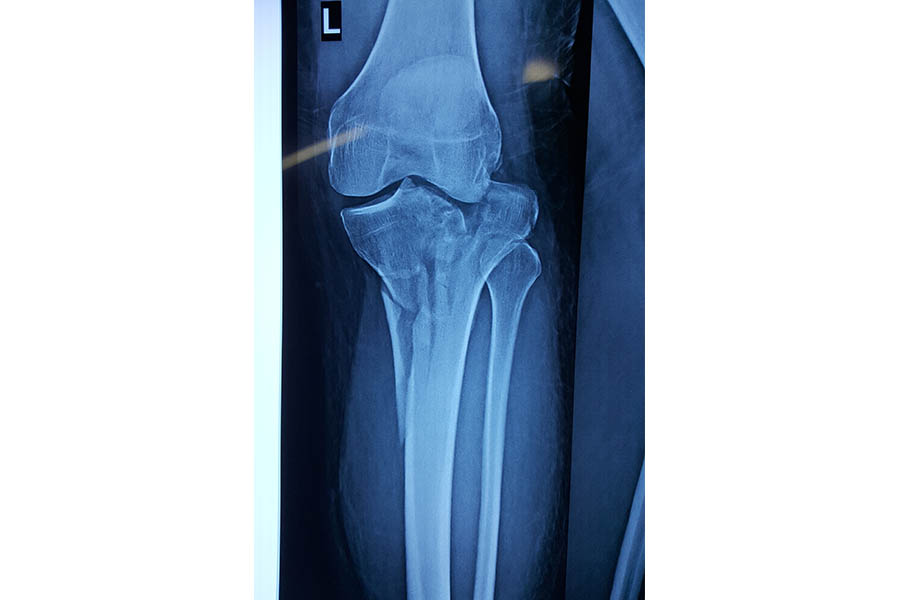

Total Knee Replacement